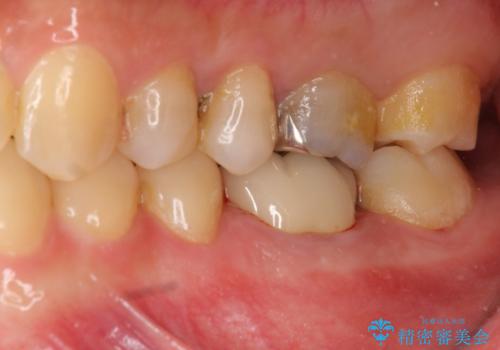

放置してしまった歯 根管治療からの機能回復

- 放置してしまった歯が痛み、いよいよ耐えられなくなり来院されました。

根管治療の途中で放置してしまっていた歯を、最終的に機能回復できるよう治療を行っていきます。

- 13万円(仮歯・ファイバーコア・ジルコニアクラウン)費用は治療当時の料金となります

治療途中の歯の放置は、より虫歯を進行させてしまい抜歯に至ってしまうこともあるので注意が必要です。